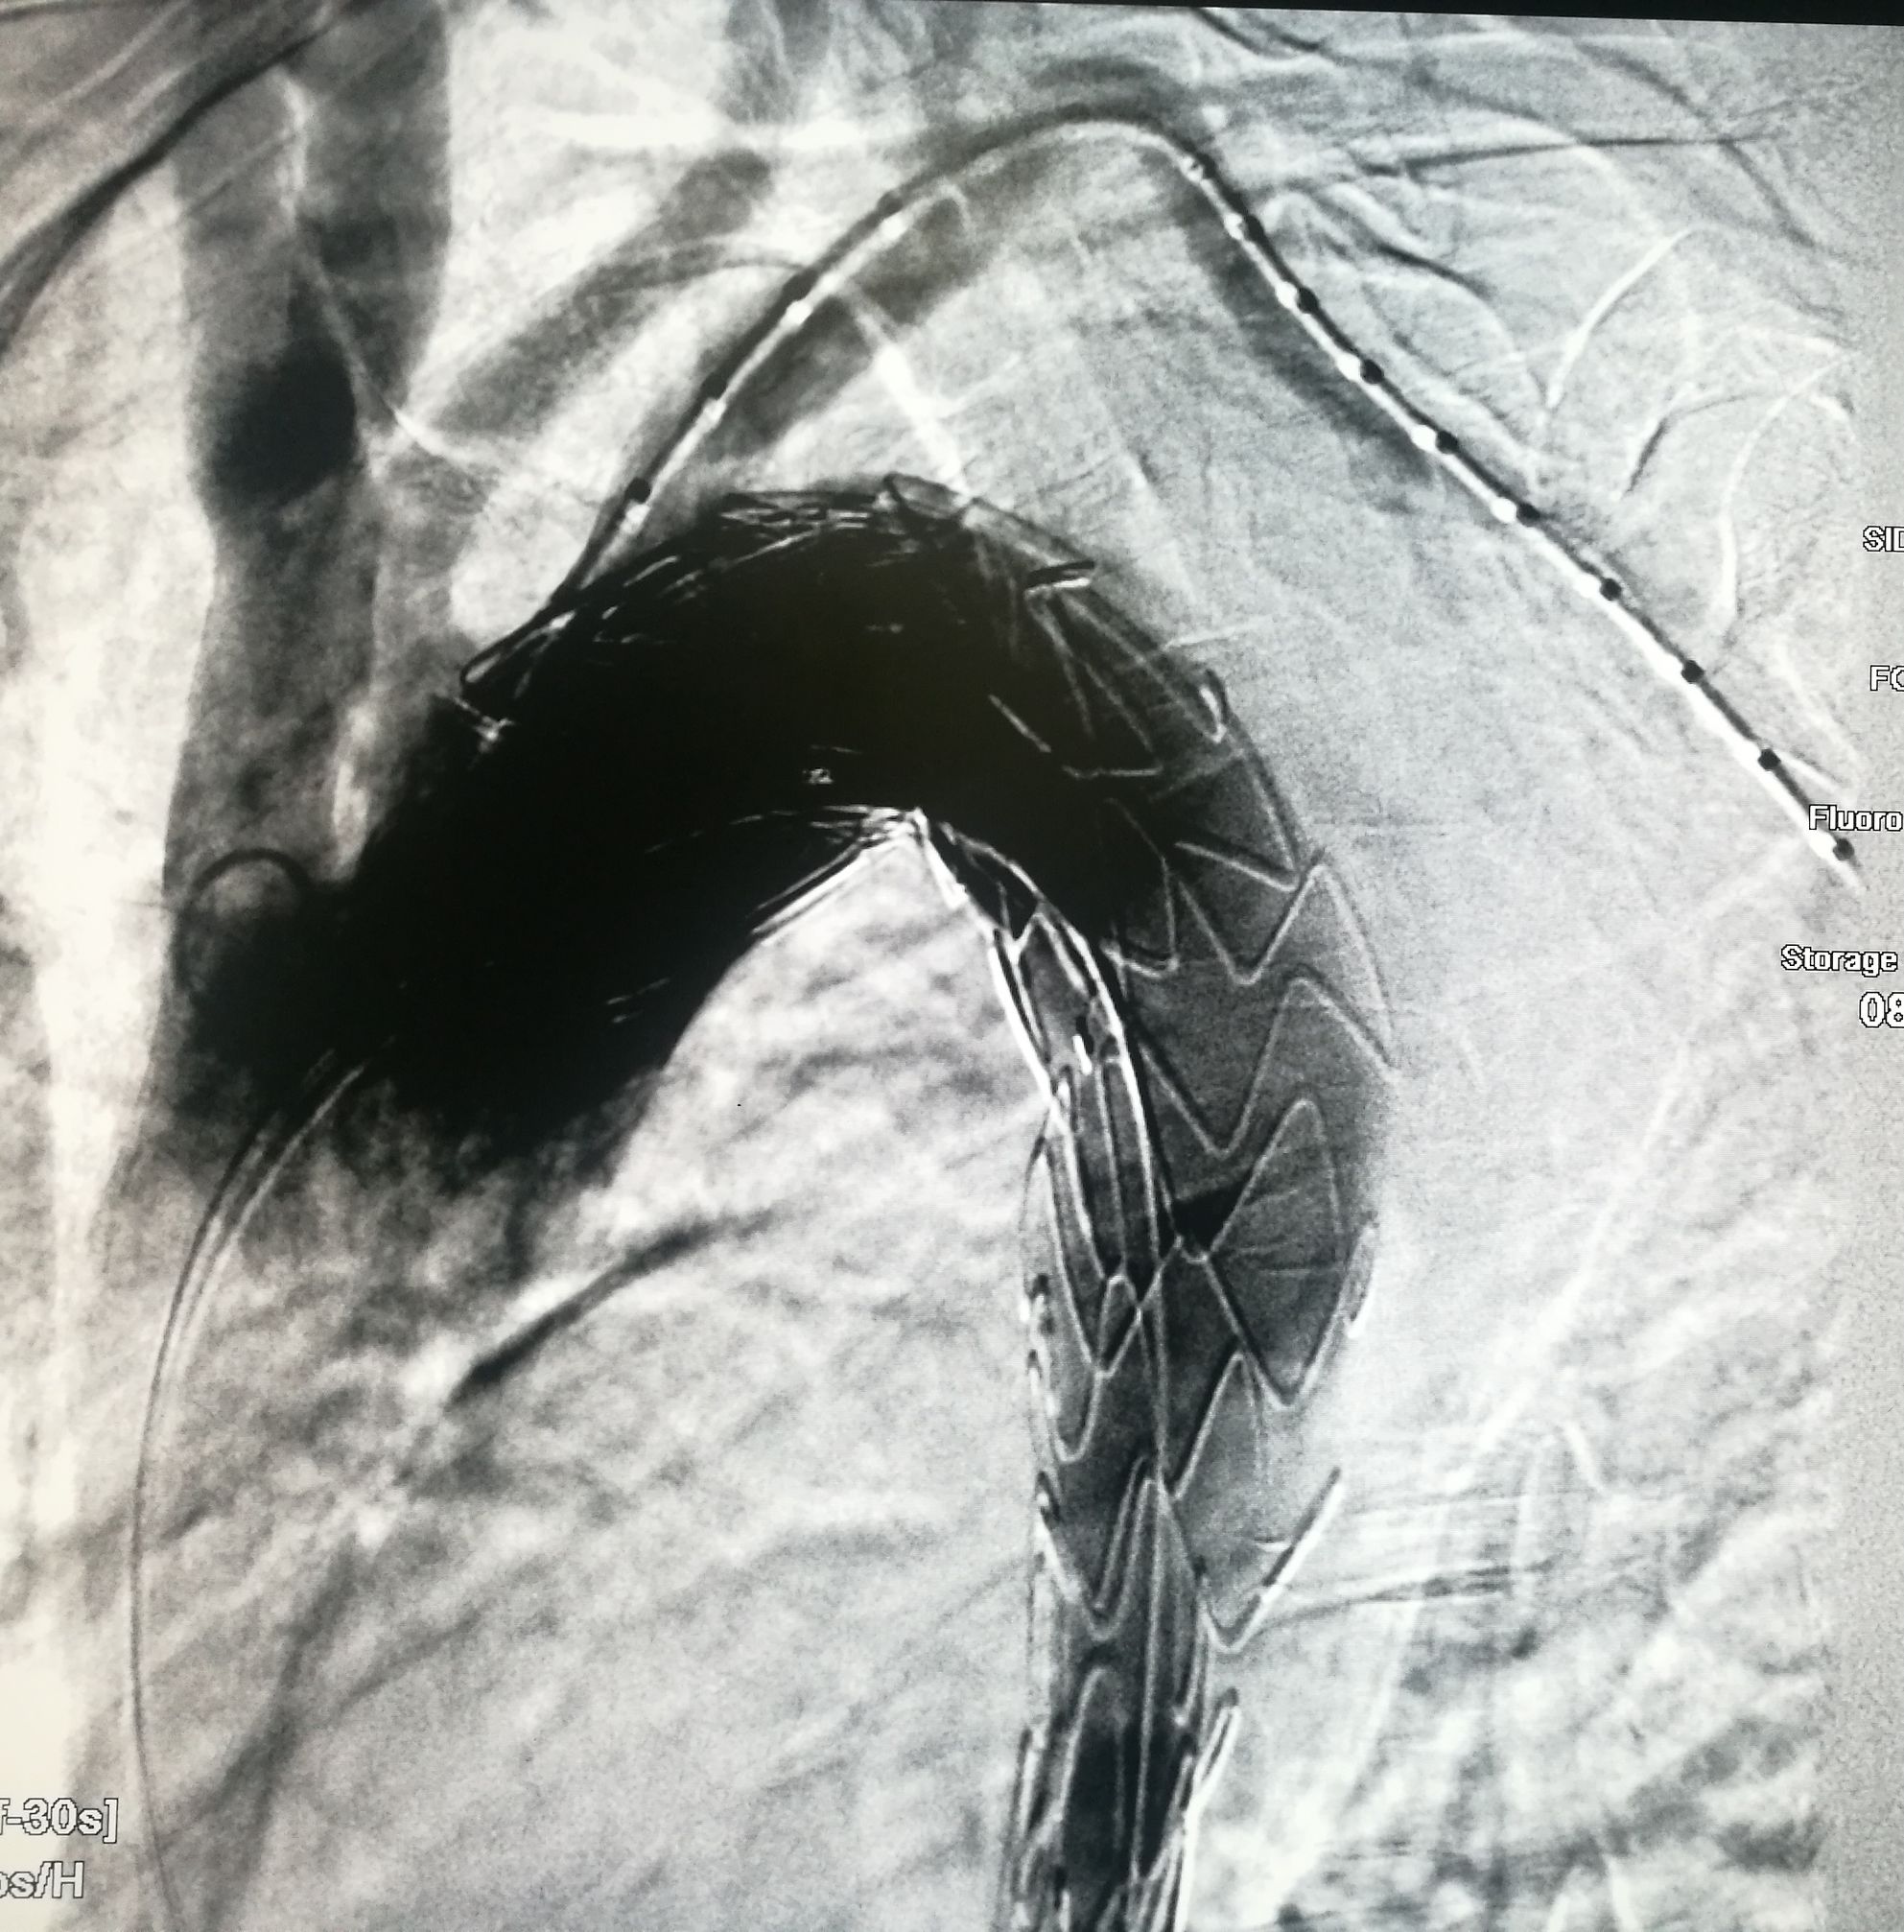

手术在局麻下进行,经右股动脉穿刺置管到升主,经左桡动脉穿刺植入金标猪尾导管,造影,为确认真假腔,加做右前斜位造影,确认股动脉导管在真腔内,测量后植入覆膜支架。由于扭曲严重(腹主,膈肌附近,弓降),支架最初并未贴服大湾侧,支架送过锁骨下动脉后适当回撤,请拉释放导丝,此时支架整体向大弯侧轻微移动,考虑应力已经得到缓解。完全释放支架,定位良好,封堵完全无内漏。

慢性夹层能封堵如此完美的少,假腔压迫导致吞咽困难的也不多,慢性夹层血管扭曲严重,手术难度较大。血管病争取早发现早治疗效果好。